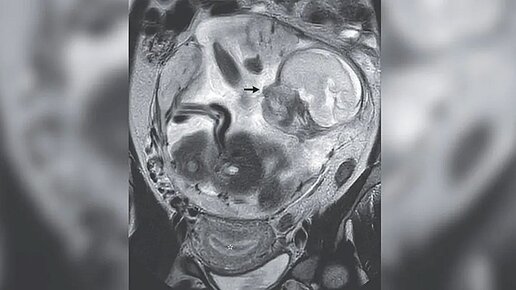

Жительница Франции обратилась в больницу с болью в животе. Оказалось, она на втором триместре редкой внематочной беременности, при которой плод рос в ее животе. Пациентка страдала от боли в животе в течение 10 дней, прежде чем обратилась за медицинской помощью в отделение неотложной помощи. После физического осмотра врачи поняли, что она беременна. УЗИ показало, что слизистая оболочка ее матки утолщилась, что обычно происходит во время менструального цикла, когда организм готовится к потенциальной беременности, а затем продолжается во время беременности...